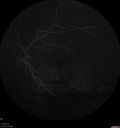

50 year old man: The patient noticed a few days ago, when putting on Contact Lenses for work which were slightly different from his usual strength. He therefore had some trouble at work with the new contact lenses. Then he had some haze in his vision. In the morning he went to see his mother in Venice and there was a new big black line in the left eye when he was getting up from lying down (this was yesterday). Then he noticed a lot of floaters in his vision that looked like blood. This has been fluctuating. You saw him this morning and asked him to come here. VA OD: Dcc20/20-2 NscJ1+ The patient has type I diabetes diagnosed at age 24 and he is now 50 years old VA OS: Dcc20/25+2 NscJ1+ IOP: TP: OD:17 OS:19

PDR and Vitreous Hemorrhage - High Risk Left Eye - Low Risk Right Eye412 views50 year old man with type I diabetes mellitus for 26 years. New Vitreous Hemorrhage in the left eye. Both eyes have NVE. Both also have foveal hypoplasia00000